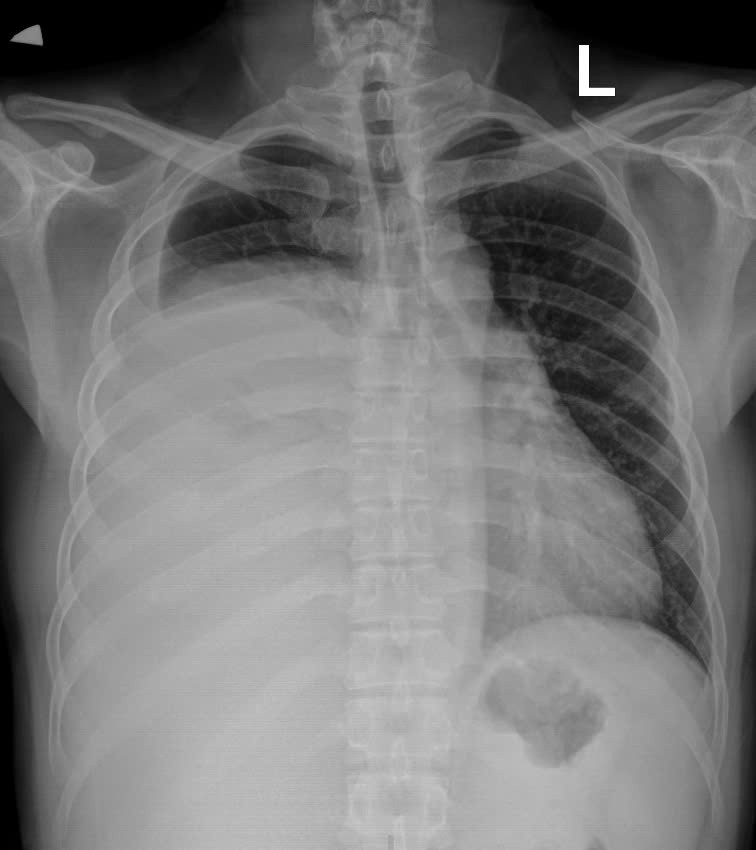

Hình ảnh phim chụp X.quang trước và sau khi phẫu thuật. (Hình trước phẫu thuật bên trái). Ảnh BVCC

Qua thăm khám và chụp cắt lớp vi tính lồng ngực, các bác sĩ phát hiện khối u trung thất khổng lồ nằm lệch trong khoang màng phổi phải, chèn ép gây xẹp gần như toàn bộ phổi phải, đẩy lệch cơ hoành. Kết quả sinh thiết xác định đây là u bao sợi thần kinh Schwannoma - Một loại u lành tính hiếm gặp xuất phát từ bao thần kinh nhưng kích thước "khủng" hiếm thấy. Khối u xâm chiếm khoang ngực, gây xẹp gần như toàn bộ phổi phải